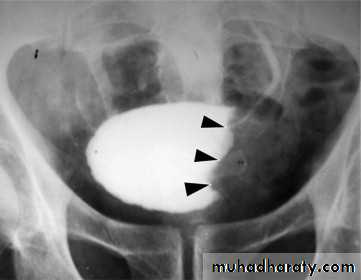

Schistosomiasis

Infestation by s.hematobium

Calcification is most important feature, mainly in bladder & lower ureters , but may involve whole ureters .

In early stage inflammation may cause cobble stone appearance.

Bladder capacity not affected.

Ddgx of bladder calcification :

1. schistosomiasis .

2.tumor , TB, …